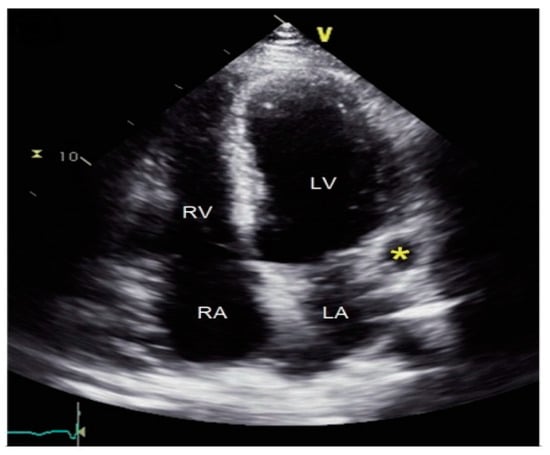

1.1. Diagnostic